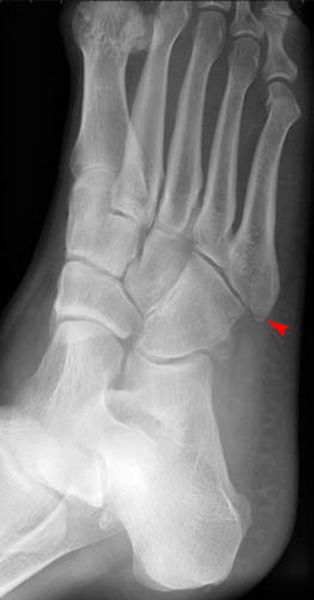

Jones Fracture

第五跖骨基底部骨折

易漏诊

不制动易致骨不连